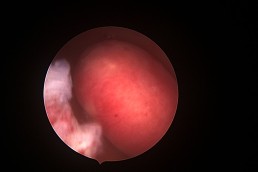

Polipii uterini

Polipii uterini reprezintă proliferări locale ale endometrului (mucoasa ce căptușește cavitatea uterină) și în marea majoritate a cazurilor sunt benigni. Ei pot provoca sângerări anormale, infertilitate sau pot interfera cu implantarea embrionilor în cursul fertilizării in vitro. Polipii endometriali pot fi diagnosticați cu ajutorul ecografiei, iar histeroscopia certifică acest diagnostic. În plus, histeroscopia permite și rezecția și extragerea polipilor endometriali. (fig. 3, 4)